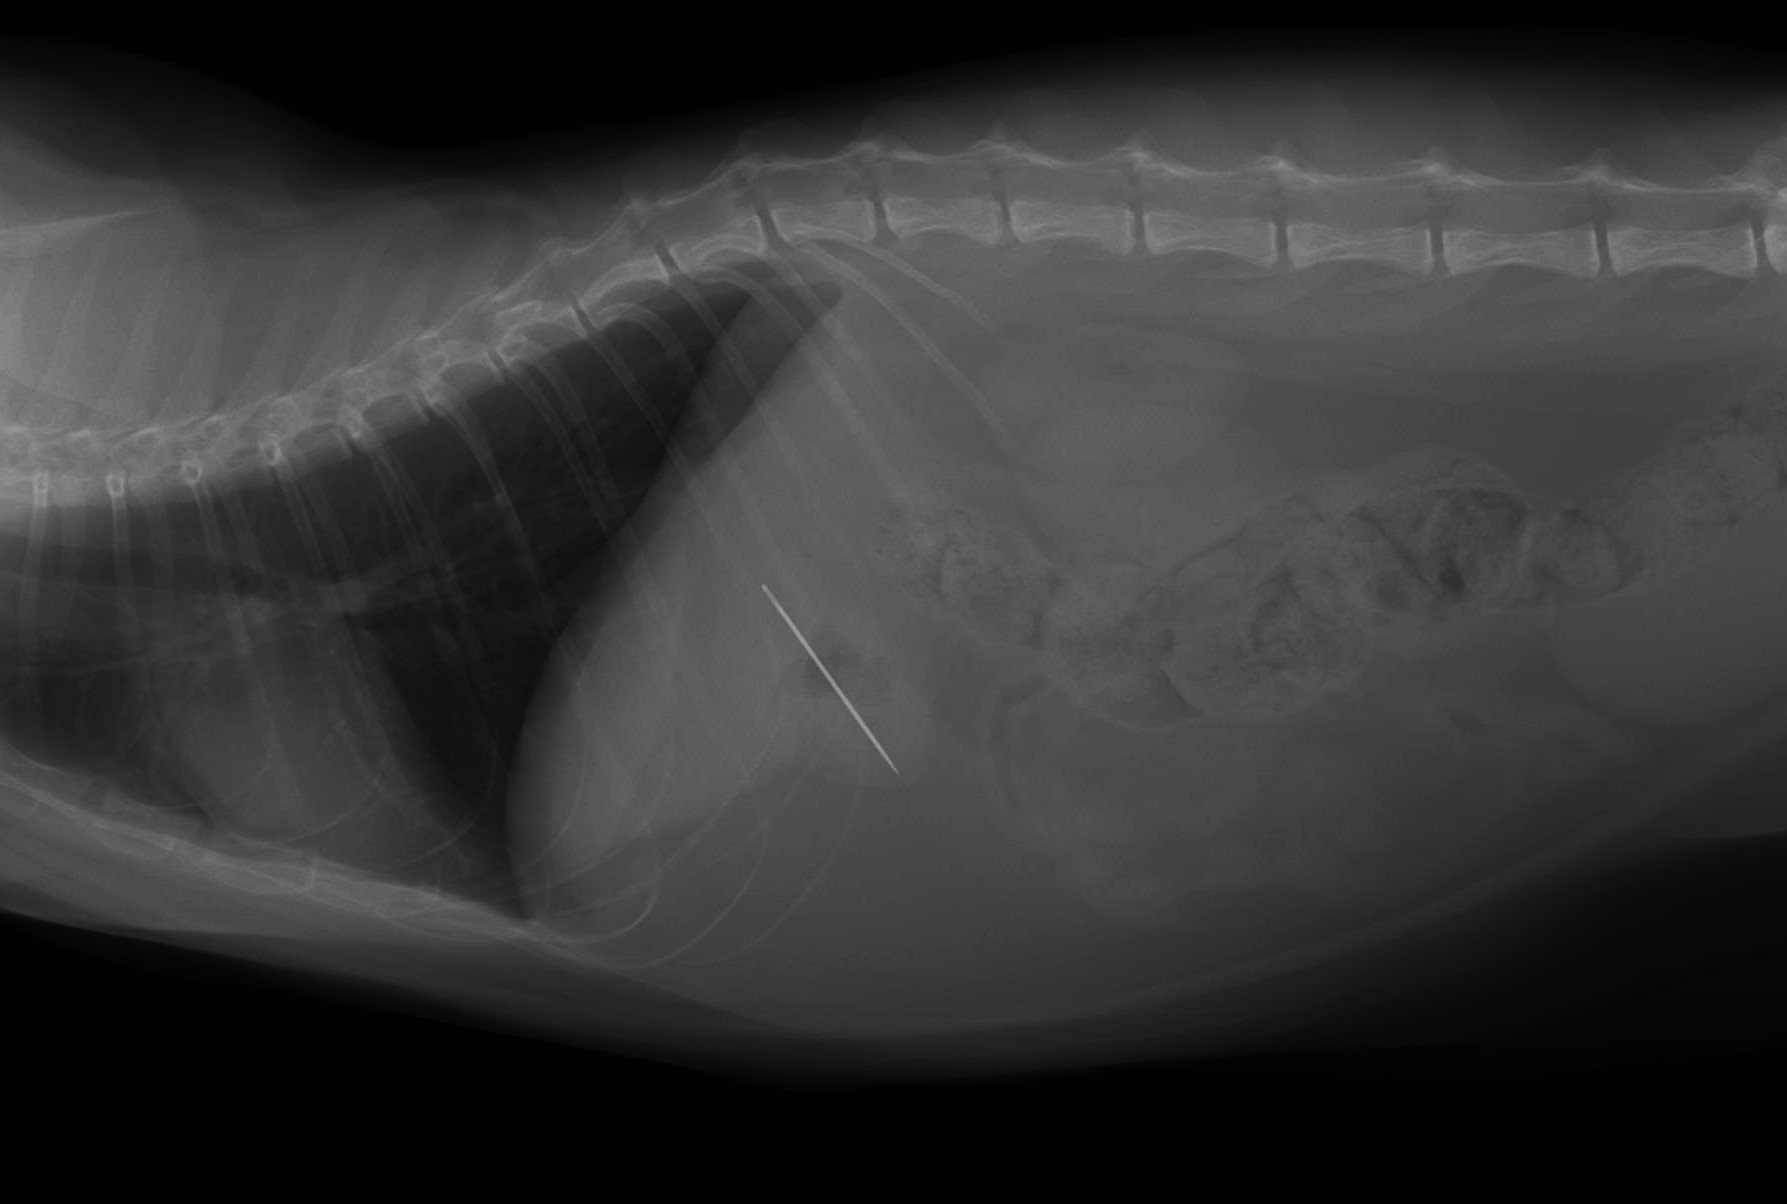

1歳ちょっとの元気な猫ちゃんで、去年の秋ごろに保護された元野良猫さんとのこと。

この猫ちゃんの体から出てきたものですが、下痢や嘔吐などの症状もなく、元気すぎるほど。

この寄生虫、名称は「マンソン裂頭条虫」というサナダムシの一種で、猫や犬の小腸に寄生します。

無症状のものから、体重減少するほどの消化器症状を呈するものと様々ですが、

もちろん治療(駆虫)が必要になります。

他の寄生虫に比べると、高用量の駆虫薬を投与することになります。

錠剤での治療も可能ですが、大量の錠数になるので注射薬での治療をお勧めします。

感染の状況によっては、複数回の駆虫が必要になることもあります。